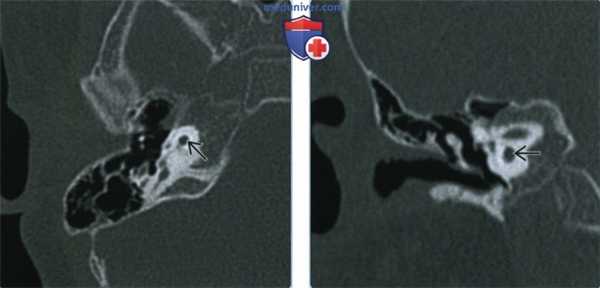

Один пациент, по данным КТ височных костей, имел двустороннюю облитерацию лабиринта, включая улитки с двух сторон, с большей выраженностью патологических изменений справа. На МРТ было выявлено уменьшение количества жидкости в улитке справа, слева количество жидкости в улитке соответствовало норме (рис. 1, 2).

Рис. 1. КТ, аксиальная проекция. Облитерация улитки (стрелка).

Рис. 2. МРТ, аксиальная проекция. Справа — полное отсутствие жидкости в улитке (короткая стрелка), слева — частичное (длинная стрелка).

У одного пациента на КТ определялись двусторонняя аномалия внутреннего уха по типу Мондини (рис. 3), двусторонний локальный порок развития цепи слуховых косточек, костная облитерация лабиринта, включая улитку справа. На МРТ внутриулитковая жидкость справа не определялась, слева количество внутриулитковой жидкости было в норме.

Рис. 3. КТ, аксиальная проекция. Аномалия Мондини, состояние после КИ.